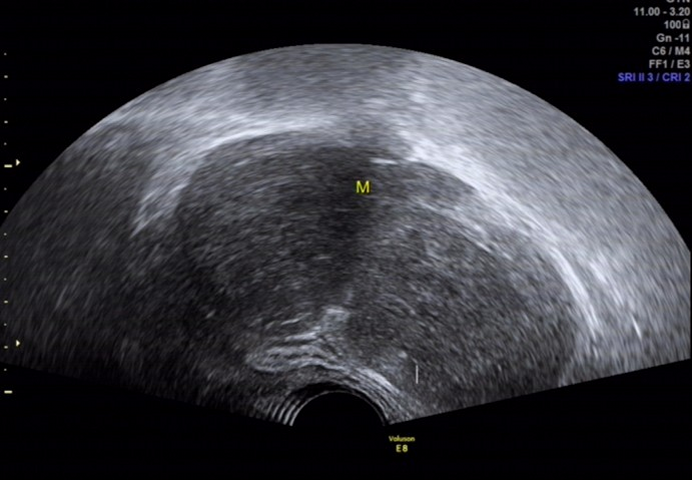

图 6 经阴道超声扫查见包块形态尚规则,与盆腔各脏器分界清楚